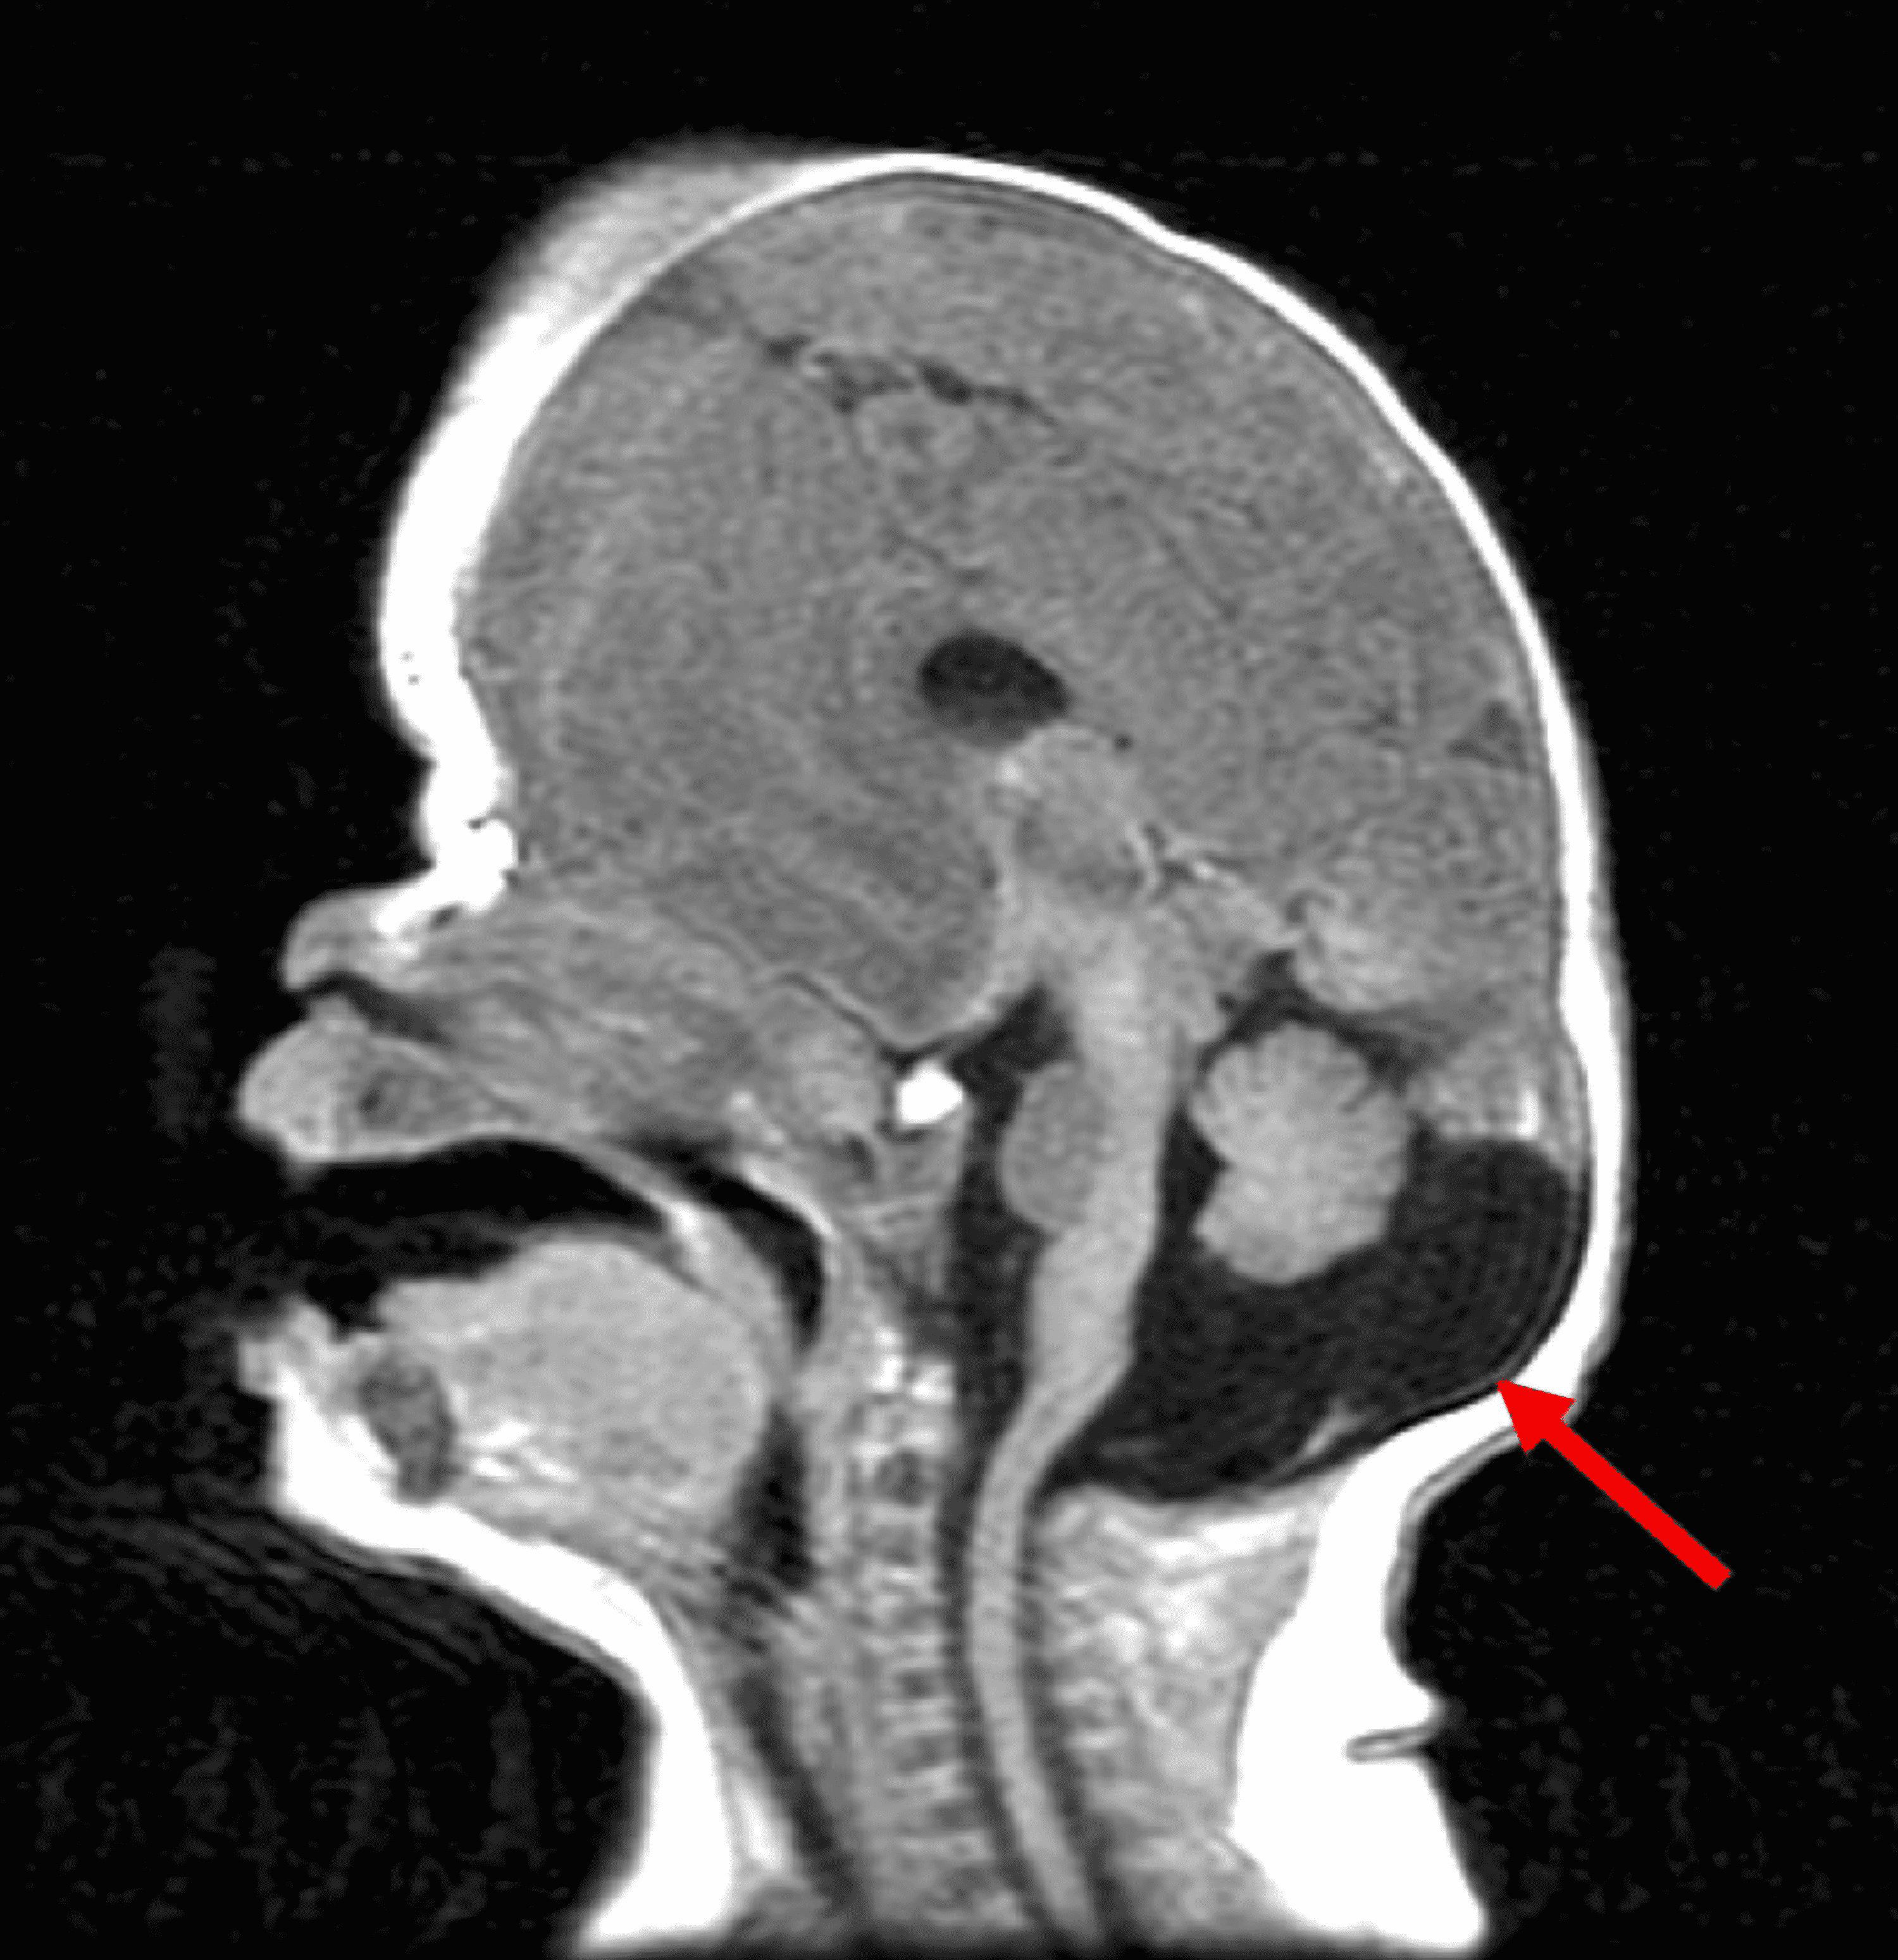

What Is Enlarged Cisterna Magna . It may be a normal variation, a. It is usually an isolated finding, but may be. Mega cisterna magna refers to a cystic posterior fossa malformation that is. Megacisterna magna is a rare brain abnormality in which the cisterna magna is larger than normal. It lies posterior to the medulla, the inferior vermis, and. What are mega cisterna magna (mcm) and arachnoid cysts (ac)? The cisterna magna is the largest subarachnoid cistern, containing from 3 to 10 ml of csf.

The cisterna magna is the largest subarachnoid cistern, containing from 3 to 10 ml of csf. Mega cisterna magna refers to a cystic posterior fossa malformation that is. Megacisterna magna is a rare brain abnormality in which the cisterna magna is larger than normal. It may be a normal variation, a. What are mega cisterna magna (mcm) and arachnoid cysts (ac)? It lies posterior to the medulla, the inferior vermis, and. It is usually an isolated finding, but may be.

What Is Enlarged Cisterna Magna It lies posterior to the medulla, the inferior vermis, and. What are mega cisterna magna (mcm) and arachnoid cysts (ac)? It lies posterior to the medulla, the inferior vermis, and. It is usually an isolated finding, but may be. The cisterna magna is the largest subarachnoid cistern, containing from 3 to 10 ml of csf. It may be a normal variation, a. Megacisterna magna is a rare brain abnormality in which the cisterna magna is larger than normal. Mega cisterna magna refers to a cystic posterior fossa malformation that is.